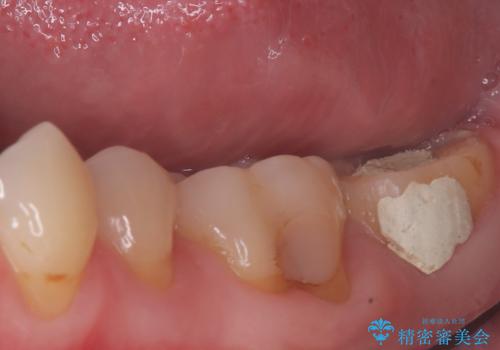

- 患者様は、他院で根管治療を受けたものの、違和感が続くため「しっかりとした治療を受けたい」とのご希望で来院されました。診査の結果、根管内の感染が完全に除去されておらず、根の先に炎症が残っている状態でした。そこで、精密根管治療を行い、感染源を徹底的に除去する計画を立てました。マイクロスコープを使用し、4回の治療で根の内部を清潔にし、最終的にしっかりと密封することで、長期的な安定を目指しました。

治療は、まず根管内の古い充填材を取り除き、感染部分を徹底的に洗浄・消毒することから始めました。ラバーダム防湿を使用し、治療中の細菌感染を防ぎながら、マイクロスコープを用いて根管の細部まで確認しながら処置を進めました。4回の治療で感染の除去と根管の封鎖を行い、最終的に土台を立てて被せ物の準備を整えました。患者様からは「違和感がなくなり、噛んでも痛くない」と喜びの声をいただきました。